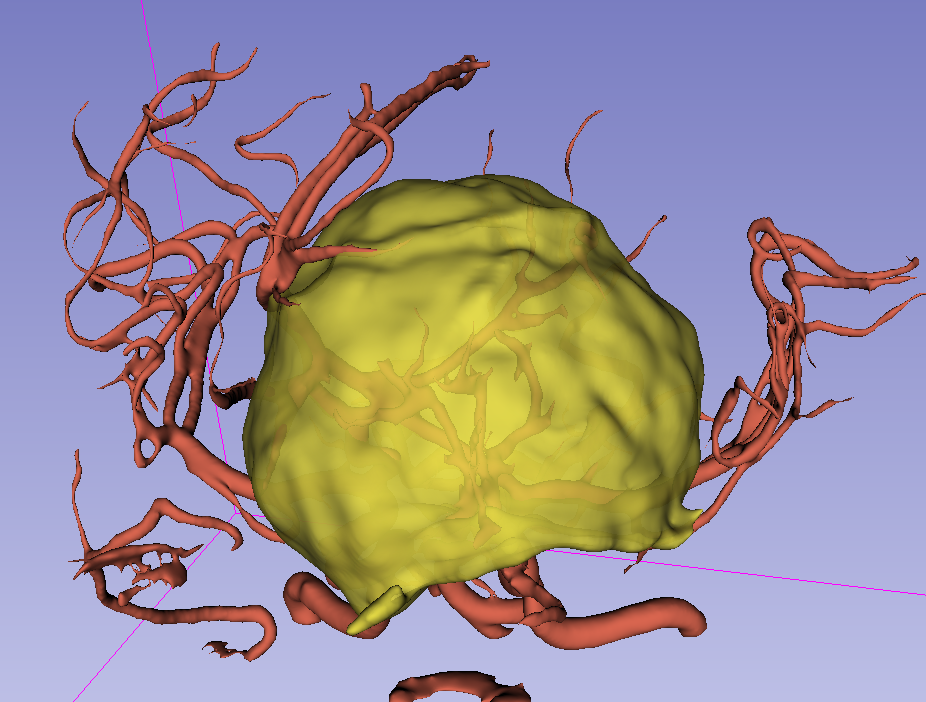

前颅窝底脑膜瘤常起源于前颅底筛骨筛板处的硬膜,瘤体多为双侧生长,少数为偏侧生长,女性稍多于男性。肿瘤可累及鸡冠和蝶骨平台的任何区域,是前颅窝肿瘤中最多见的一种。因为肿瘤位于前颅窝底,额叶在功能上属于“哑区”,患者就诊发现肿瘤时瘤体多已巨大。主要症状可有颅内压增高症状、视力减退、癫痫以及精神症状等。该患者主因“左眼失明10个月,头痛3个月”就诊。术中采用双额冠状开颅,左侧为主,由于肿瘤体积巨大,术中切除少许薄层额叶脑组织,边离断基底、边瘤内减压,分块切除肿瘤,最终探查肿瘤基底主要位于鸡冠、筛板、蝶骨平台、鞍结节、前床突处硬膜,术中见肿瘤供血主要来源于前颅窝底硬膜及大脑前动脉分支,术中仔细辨认供血动脉、过路血管,大脑前动脉及其分支保护完好,术中见视神经、视交叉受压明显,尤其是左侧视神经已缺血苍白,最终达Simpson II级切除。术者体会,该患者术前行多模态重建,可见瘤表数条粗大的静脉,术中切莫过早离断肿瘤的引流静脉,以防因引流不畅致瘤体肿胀出血;术前行多模态重建,利于鉴别供血动脉、过路血管,早期离断供血动脉更利于肿瘤切除;该类肿瘤基底一般较为广泛,不能盲目离断基底,尤其是近鞍结节处,可以于中线处离断基底,进入第一间隙后向两侧探查并保护视神经,待充分缩小瘤体看清楚毗邻的血管神经后再将其完全切除;术毕做好多层颅底重建以防脑脊液漏。另外,该患者术前左眼失明已达10个月,术后第1天即有光感,术后1月复查左眼视力可达50cm内数指,这在临床中非常少见,对于此类病人,不要轻易放弃挽救视力的任何机会。